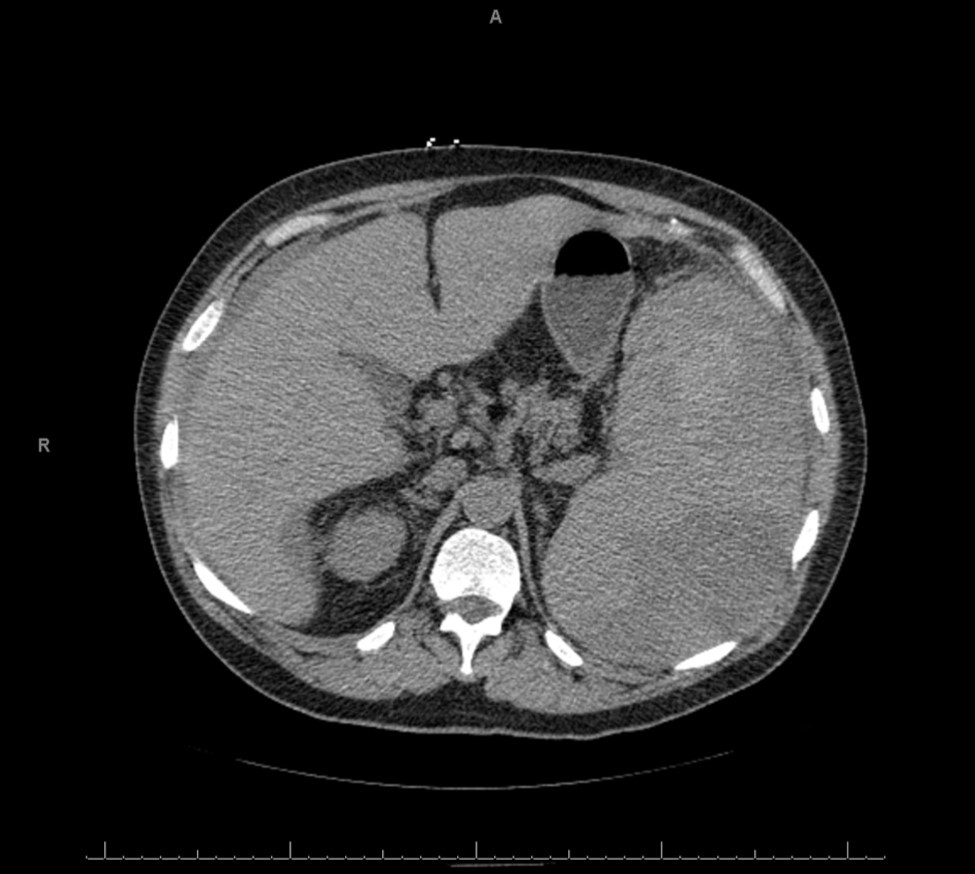

A plain abdominopelvic CT showed massive splenomegaly with high attenuation areas suspicious for hematoma, as well as free fluid in the abdomen (Figure 1). The patient was immediately started on a transfusion of packed red blood cells and taken emergently to the operating room. A laparotomy was performed and the patient was found to have a massive, ruptured spleen with 1500 mls of frank blood in the peritoneal cavity. Splenectomy and abdominal washout were done. The spleen measured 21 x 19 x 10 cm and weighed 2870 grams. It is shown below (Figure 2).

Figure 1.CT image of the abdomen showing the enlarged spleen. The arrows point to areas of higher attenuation suspicious for hematoma